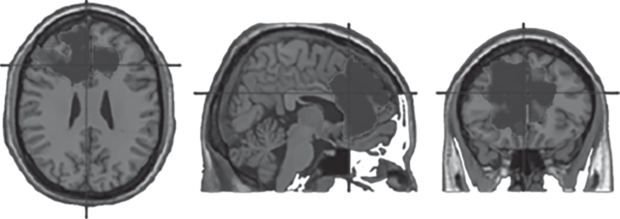

Регрессия оценок тревожности на контраст ДС > СВ не выявила достоверных эффектов. Регрессия оценок тревожности на контраст ДС < СВ выявила достоверный кластер с центром в передней части поясной извилины (рис. 2).

Регрессия оценок руминации на контраст ДС > СВ выявила достоверный кластер в правой париетальной области (рис. 3). Регрессия оценок шкалы руминации на контраст ДС < СВ не выявила достоверных эффектов.

В то же время депрессивная симптоматика в нашей выборке коррелировала с доминированием СВ над ДС в передней части поясной извилины. Эта область коры участвует в широком спектре процессов, связанных с принятием решений и контролем поведения, в том числе с контролем эмоциональных реакций. Интересно, что для тревожности выявлен только последний эффект. Доминирование СВ в этой области мозга может свидетельствовать о склонности принимать решения, ориентируясь на внешние обстоятельства. Это может быть связано с состоянием настороженности, характерным для тревожных индивидов. Таким образом, можно думать, что общим для депрессии и тревожности является состояние настороженности, которое отражается в доминировании СВ в сфере принятия решений, а специфичными для депрессивной симптоматики и руминации являются процессы эмоциональной интроспекции, отражающиеся в доминировании ДС в сфере обработки эмоциональной информации. При интерпретации этих данных нужно иметь в виду, что наша выборка состояла из здоровых испытуемых, у которых депрессивная симптоматика не доходит до клинического уровня. Можно предположить, что на стадии клинической депрессии проявления, связанные с тревожностью, могут уже играть меньшую роль и доминирующим становится процесс эмоциональной руминации.